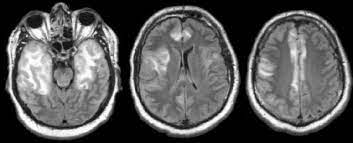

Lesions similar to cytotoxic edema, and lesions similar to vasogenic edema. Seizure, altered sensorium, fever frontal and temporal lobes, rarely extratemporal t2 hyperintensity, restricted diffusion, sometimes. Herpes encephalitis is the most common sporadic encephalitis in the united states and other industrialized countries .occurring as either a primary infection with herpes simplex virus or as a reactivation of latent virus, herpes encephalitis causes significant morbidity and mortality .early intervention with acyclovir significantly improves outcome; The clinical syndrome is often characterized by the rapid onset of fever, headache, seizures, focal neurologic signs, and impaired consciousness 1 . Having said that, mri with contrast is considered the most sensitive imaging modality, and findings are present in over half of individuals 8. The patients with the former type of lesions had fulminating disease, and were in severe clinical condition. Herpes simplex encephalitis occurs as 2 distinct entities: 4 it was found that, rather surprisingly, varicella zoster virus (vzv), the cause of chickenpox and herpes zoster, was the most frequently detected virus at 29%, with hsv and enteroviruses accounting for 11% of cases. Two subtypes are recognized which differ in demographics, virus, and pattern of involvement. (1)department of radiology, ankara numune education and research hospital, ankara, turkey. Neonatal herpes simplex encephalitis is caused by vertical transmission of infection during passage from birth canal with diffuse cerebral involvement within the first month after birth; As the older term limbic encephalitis implies, the most common location of involvement is the mesial temporal lobes and limbic systems, typically manifested by cortical thickening and increased t2/flair. In patients with herpes encephalitis, two distinct types of diffusion imaging findings (on b =1000 s/mm 2 images, and adc maps) were noted:

We present mri findings of two cases of herpes simplex encephalitis (hse) confirmed by pcr analysis, focusing on the serial changes after acyclovir therapy: 4 it was found that, rather surprisingly, varicella zoster virus (vzv), the cause of chickenpox and herpes zoster, was the most frequently detected virus at 29%, with hsv and enteroviruses accounting for 11% of cases. mri findings of herpes simplex encephalitis. For viral infection of the meninges, please refer to the general article on viral meningitis, and, for a broad view on the curriculum of infections of the central nervous system, refer to cns. The patients with the former type of lesions had fulminating disease, and were in severe clinical condition. The kappa value for interobserver agreement on rating the scans as normal or abnormal was good (0.65) for ct and moderate (0.59) for mri. Noguchi t, yoshiura t, hiwatashi a, et al. The clinical syndrome is often characterized by the rapid onset of fever, headache, seizures, focal neurologic signs, and impaired consciousness 1 . The patients with the former type of lesions had fulminating disease, and were in severe clinical condition. Specific diagnosis often requires pcr. As the older term limbic encephalitis implies, the most common location of involvement is the mesial temporal lobes and limbic systems, typically manifested by cortical thickening and increased t2/flair. In patients with herpes encephalitis, two distinct types of diffusion imaging findings (on b =1000 s/mm 2 images, and adc maps) were noted: A recent study in finland also used pcr to detect various viruses in the csf of over 3000 patients who had infections of the cns including encephalitis, meningitis, and myelitis.

(1)department of radiology, ankara numune education and research hospital, ankara, turkey. article in japanese yoshioka a, hirose g, tsukada k, oda r, kosoegawa h. Two subtypes are recognised which differ in demographics, virus, and pattern of involvement. Seizure, altered sensorium, fever frontal and temporal lobes, rarely extratemporal t2 hyperintensity, restricted diffusion, sometimes. Encephalopathy from herpes simplex encephalitis (hse). Specific diagnosis often requires pcr. Having said that, mri with contrast is considered the most sensitive imaging modality, and findings are present in over half of individuals 8. We present mri findings of two cases of herpes simplex encephalitis (hse) confirmed by pcr analysis, focusing on the serial changes after acyclovir therapy:

The patients with the former type of lesions had fulminating disease, and were in severe clinical condition. The diagnosis of hse is based on laboratory investigations, magnetic resonance (mr) imaging findings, electroencephalogram and, occasionally, a biopsy. Herpes encephalitis is the most common sporadic encephalitis in the united states and other industrialized countries .occurring as either a primary infection with herpes simplex virus or as a reactivation of latent virus, herpes encephalitis causes significant morbidity and mortality .early intervention with acyclovir significantly improves outcome; Herpes simplex (hsv) encephalitis is the most common cause of fatal sporadic fulminant necrotising viral encephalitis and has characteristic imaging findings. In patients with herpes encephalitis, two distinct types of diffusion imaging findings (on b =1000 s/mm 2 images, and adc maps) were noted: Relapse of encephalitis occurs in up to 10% of patients, manifested by recurrent symptoms, clinical and mri findings, and the presence of herpes simplex virus type 1 dna in the cerebrospinal fluid (csf). In children older than 3 months and in adults, hse is usually localized to the temporal and frontal lobes and is c. In patients with herpes encephalitis, two distinct types of diffusion imaging findings (on b =1000 s/mm 2 images, and adc maps) were noted: Herpes simplex (hsv) encephalitis is the most common cause of fatal sporadic fulminant necrotizing viral encephalitis and has characteristic imaging findings. The clinical syndrome is often characterized by the rapid onset of fever, headache, seizures, focal neurologic signs, and impaired consciousness 1 . We present mri findings of two cases of herpes simplex encephalitis (hse) confirmed by pcr analysis, focusing on the serial changes after acyclovir therapy: Two subtypes are recognised which differ in demographics, virus, and pattern of involvement. Despite advances in antiviral therapy over the past 2 decades, herpes simplex encephalitis (hse) remains a serious illness with significant risks of morbidity and death.